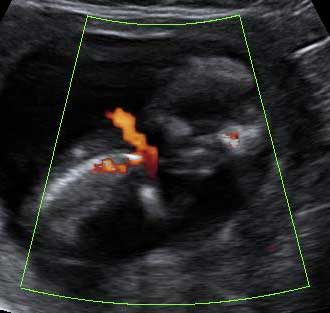

Ecografía 4D de la 12 semanas: Feto con cordón umbilical al hombro

Puede tener una vuelta de cordón al cuello

Este bebé, cuya edad gestacional es de sólo 12 semanas, muestra una gran vitalidad de movimientos, a pesar de que el cordón umbilical está peligrosamente situado a la altura del hombro y probablemente alrededor del cuello. El feto parece estar peleándose, como si intentara liberarse de la "atadura" del cordón umbilical.

Ecografía 4D de feto de 12 semanas con cordón umbilical al hombro